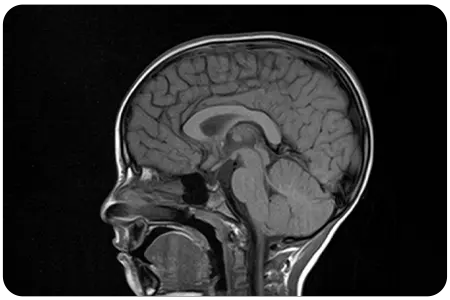

MRI is a non-invasive imaging technique that uses powerful magnets and radio waves to create detailed images of soft tissues, offering unparalleled insight into the anatomy and functionality of the velopharyngeal mechanism.

Our specialists use MRI to precisely diagnose Velopharyngeal Dysfunction (VPD) and develop effective, individualized treatment plans.